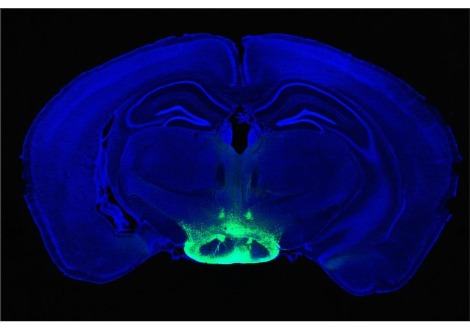

زرع فريق علي المخاريط في شبكية عين الفئران التي تمت تربيتها لتطوير مرض متقدم في العين ، مع وجود مخاريط غير وظيفية تمامًا. باستخدام هذه الفئران التي تم التحكم فيها لاحتمال أن الوظيفة المتبقية من المخاريط الموجودة ، بدلاً من المخاريط المزروعة حديثًا ، كانت مسؤولة عن أي تحسينات في الرؤية. للتأكد من أن الفئران لم تشن دفاعًا مناعيًا ضد الخلايا البشرية ، تم تربيتها أيضًا لتكون تعاني من نقص المناعة.

قام الباحثون بحقن المخاريط الوظيفية في شبكية عين 32 عين فأر ، والمخاريط الشاذة في 23 عينًا أخرى. في بعض الأحيان ، تلقت عين الفأر عمليات الزرع ، وأحيانًا واحدة فقط. كلا النوعين من المخاريط ، سواء كانا يعملان أم لا ، متصلان بشبكية العين لتكوين كتلة خلوية نموذجية للعين السليمة وضرورية للرؤية في الضوء الساطع.

لكن أوجه التشابه انتهت بمجرد أن عرّض الباحثون الفئران للضوء. استجابت شبكية عين الفئران ذات المخاريط البشرية الوظيفية للضوء أثناء اختبار العين المصمم لقياس هذا ، والمعروف باسم الرسم الكهربي الدقيق للشبكية ، بينما لم تستجب شبكية العين لدى أولئك الذين لديهم مخاريط مختلة وظيفيًا. في اختبار آخر ، اختارت الفئران التي تلقت المخاريط الوظيفية التراجع إلى غرفة مظلمة عندما أعطيت الخيار ، وهو مؤشر على أن الحيوانات الليلية كانت تستشعر الضوء وتتجنبه كما تفعل الفئران عادة. على النقيض من ذلك ، بقيت الفئران ذات المخاريط المعيبة في الضوء لجزء كبير من الوقت.